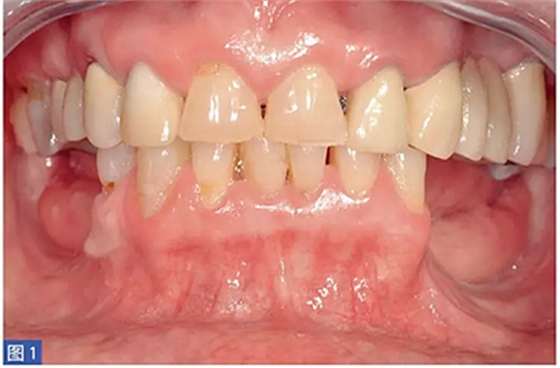

圖1:病例1. 術(shù)前照,59 歲非吸煙者女性,左下頜牙槽嵴重度萎縮。